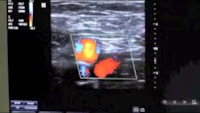

Esistono poi dei piccoli trucchi per verificare che non vi sia ostruzione sia al di sotto che al di sopra della vena femorale. Anche in questo caso il presupposto teorico è intuitivo .Se esiste flusso che arriva a tale livello, lo possiamo dimostrare attraverso l’uso del colore o del doppler.

In pratica cosa facciamo: dopo aver identificato la vena femorale comune, mettiamo il colore e schiacciamo rapidamente il polpaccio omolaterale (squeezing) con l’altra mano o, ancora meglio, ci facciamo aiutare in questa manovra da un assistente . In assenza di ostruzione vedremo un cospicuo aumento del colore a livello della vena stessa.